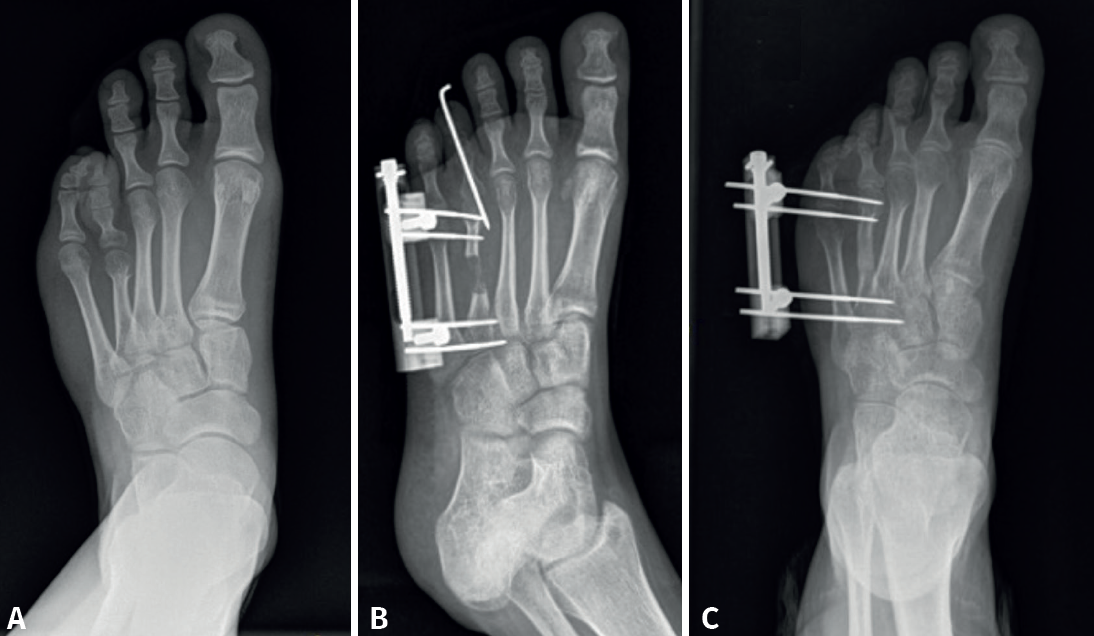

En el grupo A se realizó un alargamiento gradual mediante callotasis con fijador externo. Generalmente, se trataba de aquellos pacientes en los que se necesitaba alargar más de 15 mm debido a la potencial limitación de las partes blandas en el caso de alargamiento en un tiempo. Para ello se utilizó un minifijador externo monorraíl (MiniRail® Orthofix MBA). La técnica quirúrgica consistió en realizar una incisión dorsal sobre el metatarsiano afectado, seguida de un alargamiento del tendón extensor largo mediante Z-plastia y tenotomía del extensor corto. Posteriormente, se introdujeron 2 o 3 agujas roscadas de 2 mm proximales y otras 2 o 3 distales al sitio planificado para la osteotomía, con una angulación de 45° con respecto al plano del suelo para el segundo al cuarto metatarsiano y una angulación de 0° con respecto al plano del suelo en el caso de que se tratara del primer o quinto metatarsiano. La osteotomía se realizó en la zona más proximal posible mediante perforaciones con agujas de Kirschner, que se completaron con escoplos. A continuación, se implantó el cuerpo del fijador externo y se realizó la distracción para comprobar la apertura de la osteotomía. Posteriormente, el fijador se colocó en posición de compresión y se introdujo una aguja de Kirschner a través de la falange distal hacia la cabeza del metatarsiano con el fin de fijar temporalmente la articulación metatarsofalángica y evitar así posibles luxaciones/subluxaciones articulares durante el alargamiento.

Tras la cirugía, el fijador externo se mantuvo en la posición de compresión durante 7-10 días como periodo de latencia. Pasado este tiempo, se inició el alargamiento en la consulta externa mediante la distracción de la osteotomía con el fijador externo a razón de 0,25 mm cada 12 horas (un cuarto de vuelta del fijador) que continuó el paciente en su domicilio (Figura 1). El pie intervenido se mantuvo en descarga inicialmente y protegido con un zapato posquirúrgico de suela invertida hasta la visualización de osificación en la zona de alargamiento. Al alcanzar la longitud de alargamiento deseada, se detuvo el alargamiento, se retiró la aguja de Kirschner y se mantuvo el fijador externo hasta la visualización de callo óseo radiográfico con corticalización de este.